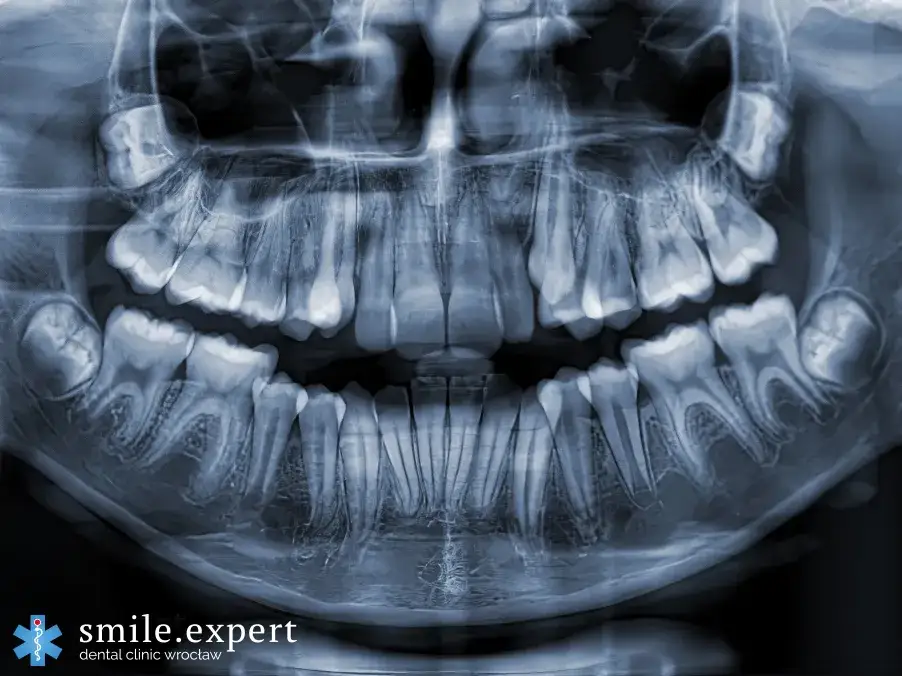

Pantomogram (panorama) to zdjęcie, które przedstawia obraz wszystkich zębów, szczęki, żuchwy, stawów skroniowo-żuchwowych oraz części zatok przynosowych na jednym zdjęciu. Jest to badanie przesiewowe, które daje ogólny obraz stanu jamy ustnej i jest często wykonywane przed leczeniem ortodontycznym, implantologicznym, czy w celu ogólnej oceny zdrowia. Dawka promieniowania jest tu nieco wyższa niż w przypadku zdjęcia punktowego, ale nadal mieści się w bezpiecznych granicach.